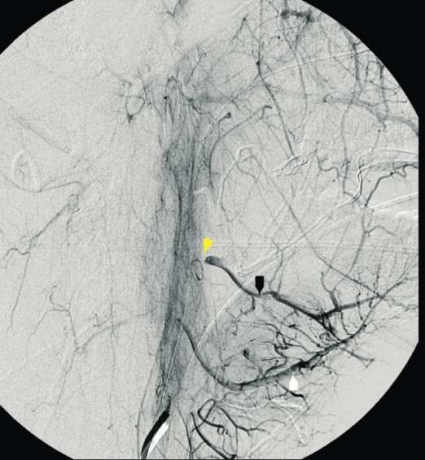

Han överförs direkt till intensivvårdsavdelningen, och inlagda kompressionstorkar fastsatta på peanger avlägsnas försiktigt. I det läget föreligger en mindre, sivande blödning basalt i vänster tonsillbädd. Det blödande området diatermeras. Eftersom det kliniska förloppet talar för en större kärlskada utförs direkt en karotisangiografi med planerad selektiv embolisering av blödningskällan. I samband med kateteriseringen av vänster arteria carotis externa börjar patienten plötsligt att blöda profust från vänster tonsillbädd. Kärlskadan lokaliseras angiografiskt till avgången för arteria facialis från arteria carotis externa (Figur 1–3). Ett första försök att stoppa blödningen selektivt i arteria facialis med intraarteriellt vävnadsklister misslyckas. Genom kraftig intern och extern kompression mot halsen kan blödningen hållas någorlunda under kontroll. I detta dramatiska läge beslutas att ockludera arteria carotis externa. Kärlet emboliseras med användande av platinacoils (Figur 4). Blödningen avstannar då omedelbart.